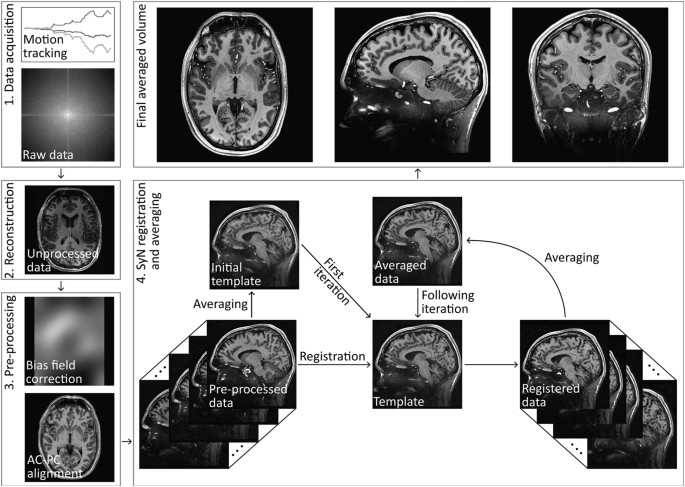

Some of the data feature the highest spatial resolution in vivo so far. However, the data is not unique due to its unprecedented spatial resolution only, but it was also acquired on the very same hardware as well as scanner's software and (mostly) with prospective motion correction to remediate rigid motion of the participant. It is quite remarkable that neither the hard- nor software was changed within these years, as this is a confounding factor in longitudinal studies commonly. Furthermore, MRI is an inherently slow acquisition technique and, therefore, is prone to motion. This becomes a particular problem when dealing with ultrahigh resolution imaging with hours of scan time to acquire a single volume. This usually leads to a deterioration of the so called effective spatial resolution. In order to still be able to capture sharp high quality images, it is therefore necessary to use a method for correcting the participant's movements. Thus, we have compiled the most comprehensive and high quality MRI data repository of a single human participant to date.

Today, we are happy to share a decade worth of MRI data of a single participant as a human phantom in our recent data descriptor published in Scientific Data available here: https://rdcu.be/clgFK. We present an extension to our previous dataset containing multiple additional contrasts with ultrahigh isotropic spatial resolution and (mostly) full brain coverage. In total, 202 volumes were acquired across 66 scanning sessions using an ultrahigh field 7 Tesla MR scanner (Siemens Heathineers, Erlangen, Germany). This includes up to 150 μm time of flight (ToF) angiography, 250 μm MPRAGE, 330 μm quantitative susceptibility mapping (QSM), up to 450 μm T2-weighted turbo spin echo (TSE), eight 700 μm T1-weighted back-to-back scans with low and high signal to noise ratio (SNR), 800 μm diffusion tensor imaging (DTI), one hour continuous 1.8 mm resting-state functional MRI (rs-fMRI), and more than 120 other MPRAGE volumes collected over 10 years with varying isotropic spatial resolution between 450 μm and 1 mm as well as many corresponding proton density weighted volumes with the same spatial resolution as the MPRAGE volumes.